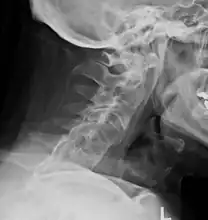

The earliest changes demonstrable by plain x–ray shows erosions and sclerosis in sacroiliac joints. Progression of the erosions leads to widening of the joint space and bony sclerosis. X-ray spine can reveal squaring of vertebrae with bony spur formation called syndesmophyte. This causes the bamboo spine appearance. A drawback of X-ray diagnosis is the signs and symptoms of AS have usually been established as long as 7–10 years prior to X-ray-evident changes occurring on a plain film X-ray, which means a delay of as long as 10 years before adequate therapies can be introduced.[19]

Lateral X-ray of the mid back in ankylosing spondylitis

Lateral X-ray of the neck in ankylosing spondylitisImaging